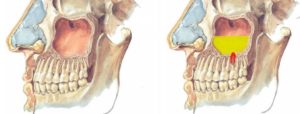

Корни зубов верхней челюсти выступают в гайморову полость. Если посчитать от центра в сторону, то с 4-го по 8-й зуб сверху ограничены гайморовой полостью.

Если пазуха склерозированная – маленькая, аккуратная, то с ней проблем бывает меньше. Если пазуха пневматический типа – широкая, то её дно огибает верхушки зубных корней.

Отсюда обоюдная взаимосвязь воспалительных процессов, протекающих в синусах либо в верхней челюсти.

А связь тут чисто анатомическая. Гайморит сам по себе — это воспаление слизистой оболочки воздухоносной пазухи, которая находится в толще верхней челюсти. Дном или нижней стенкой этой пазухи является костная прослойка, которая отделяет пазуху от корней верхних зубов (моляров и премоляров, иногда клыков).